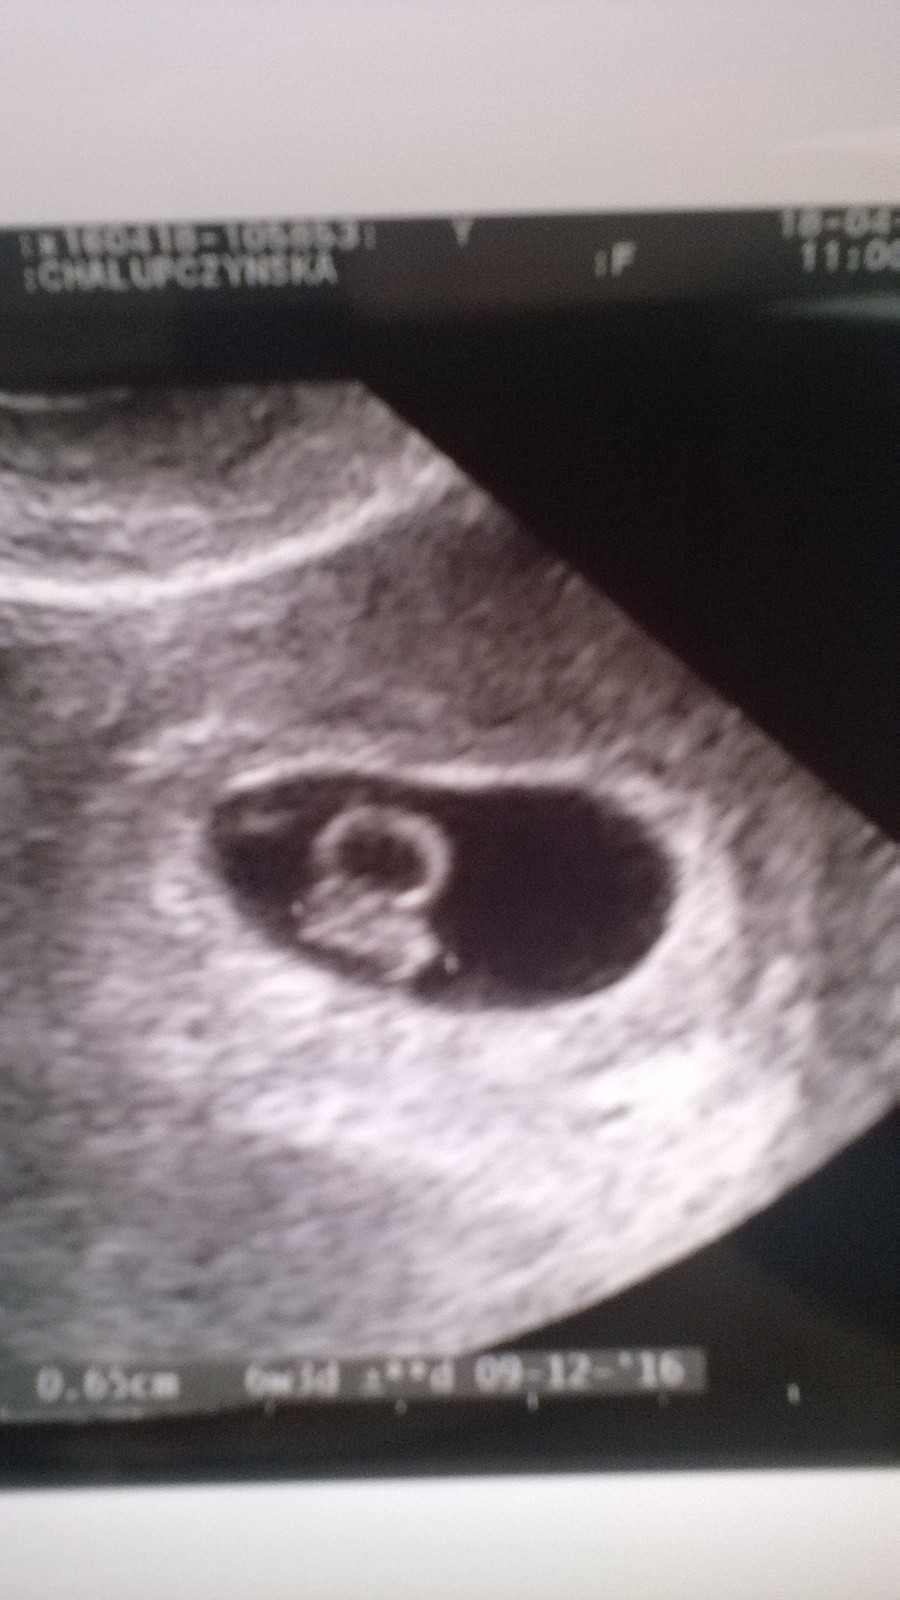

Ja juz po wizycie :) wszystko jest dobrze:) maleństwo zdrowo sie rozwija, słyszałam jak mu bije serduszko :) jestem przeszczęśliwa :) serduszko na USG pulsowalo jak oszalałe :) karta ciazy zalozona i przewidywany termin na 8 grudnia :)

Zdjęcie z USG poniżej :)